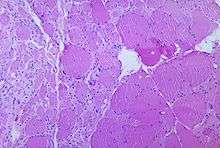

One mechanism involved in recovery is nerve terminal sprouting, in which remaining brainstem and spinal cord motor neurons develop new branches, or axonal sprouts.[67] These sprouts can reinnervate orphaned muscle fibers that have been denervated by acute polio infection,[68] restoring the fibers' capacity to contract and improving strength.[69] Terminal sprouting may generate a few significantly enlarged motor neurons doing work previously performed by as many as four or five units:[38] a single motor neuron that once controlled 200 muscle cells might control 800 to 1000 cells. Other mechanisms that occur during the rehabilitation phase, and contribute to muscle strength restoration, include myofiber hypertrophy—enlargement of muscle fibers through exercise and activity—and transformation of type II muscle fibers to type I muscle fibers.[68][70]